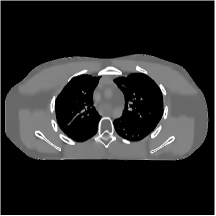

III.C.2. Simulation Framework, Reconstruction Results, and Comparisons

The synthesized low-dose clinical measurements are simulated from regular-dose images at a resolution of mm with a fan-beam CT geometry corresponding to a monoenergetic source at incident photon intensity . The sinograms are of size . The width of each detector column is mm, the source to detector distance is mm, and the source to rotation center distance is mm. We reconstruct images of size with the pixel size being mm mm.

We conducted experiments on one test slice used for parameter tuning (L067-slice 120) and four independent test slices (L109-slice 90, L192-slice90, L333-slice140, L506-slice 100) of the Mayo Clinic data. For PWLS-EP, we ran iterations using relaxed OS-LALM and set regularization parameter . We used the same as the phantom experiments for Algorithm 2. The process of selecting a general set of reconstruction parameters () for the Mayo Clinic test slices is identical to that for the XCAT phantom in Section III.B.2. The selected regularization parameter and the parameters that control the sparsity of the coefficient maps are for ST, , , , , for MARS2, , , , , , , for MARS3, , , , , , , , , , , for MARS5, and , , , , , , , , , , , , , , for MARS7, respectively.

Figs. 8, 9, 10, and 11 show the reconstructions of the four independent slices using the FBP, PWLS-EP, PWLS-ST, PWLS-MARS2, PWLS-MARS3, PWLS-MARS5, and PWLS-MARS7 schemes, respectively. Additional Mayo Clinic experimental results of the parameter tuning case (Fig. 15) are shown in the supplementary document. Table 1 lists the RMSE and SSIM values of reconstructions of the four independent test slices, with the best values bolded. Generally, the five and seven layer models provided the best RMSE and SSIM values. They outperform the single-layer model by HU in RMSE on average. However, the MARS5 and MARS7 models perform similarly. In order to strengthen the benefits of the multi-layer model, Table 2 lists the RMSE of the reconstructions in four different ROIs (shown in the reference of Fig. 11) with seven methods for slice 100 of patient L506. By observing the reconstructed images, we see that although the ST model achieves a cleaner reconstruction result than FBP and PWLS-EP, it still sacrifices some sharpness of the central region and suffers from loss of details. The deeper models have a somewhat more positive effect in terms of maintaining subtle features, which is clearly more essential to clinical diagnosis. Furthermore, as we will discuss later, after considerable parameter tuning, we found that the information contained in residual maps is gradually decreased with the number of layers, eventually vanishing at some layer, which suggests that very deep unsupervised models might not offer significantly better image quality.